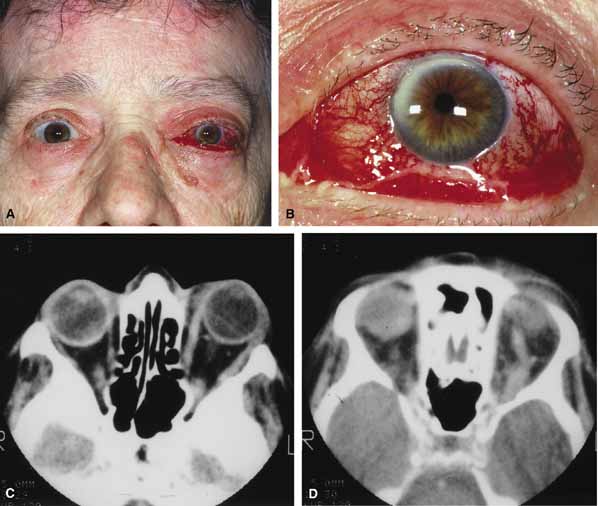

In some patients the orbitopathy is more aggressive and rapidly evolving with acute proptosis over 1 to 2 days, swelling of the lids and conjunctiva, diplopia, corneal exposure, and optic neuropathy (Fig. 6A). This presentation may be confused with disorders such as nonspecific orbital inflammation or carotid-cavernous fistula.44 The differential diagnosis of acute proptosis with enlarged extraocular muscles includes thyroid orbitopathy, vascular causes (arteriovenous fistulas), inflammation (orbital myositis, sarcoid), infection, primary invasive tumor, metastasis to the extraocular muscles.45,46

Fig. 6 A. A 56-year-old female presented with a 2-day history of proptosis, lid swelling, conjunctival chemosis/injection, and double vision. Thyrotropin (TSH) level was extremely low and a computed tomography (CT) scan revealed grossly enlarged extraocular muscles. A diagnosis of acute thyroid eye disease was made. B. Axial computed tomographt (CT) scan illustrating diffuse enlarged extraocular muscles characteristic of thyroid eye disease. C. Coronal computed tomography (CT) scan showing enlargement of extraocular muscles.

CT classically reveals enlarged extraocular muscles (Fig. 6B and 6C). One or all of the muscles may be involved and there is bilateral involvement in the majority. The most frequently involved muscle is the inferior rectus followed by the medial, superior, and lateral rectus (opposite to the spiral of Tillaux).40 The tendons of the affected recti muscles are typically not thickened, resulting in a characteristic fusiform enlargement of the muscle, whereas in myositis secondary to nonspecific orbital inflammation the tendons are generally thickened. Other signs are also useful to distinguish between the two. Bilaterally is unusual in myositis but common with thyroid. Thyroid usually has several muscles involved while myositis more often only has one muscle involved. In myositis the muscle border is more likely to be irregular or fuzzy with or without involvement of adjacent fat whereas in thyroid disease the muscle border is regular and there is no fat involved. Clinically there are also several distinguishing features. Myositis classically presents more rapidly and is associated with pain on extraocular movement. This is rare with thyroid eye disease. The eyelid signs (retraction, flare) are common with thyroid but absent in myositis.